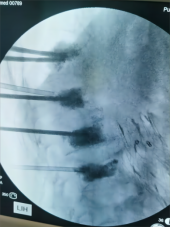

5.微创胸腰椎固定融合技术

微创胸腰椎固定融合技术适用于治疗腰椎间盘突出症、腰椎管狭窄症、腰椎失稳、腰椎滑脱、胸腰椎骨折、腰椎峡部不连及部分翻修手术等。其与传统TLIF技术相比,该技术通过最小的创伤即能达到和开放腰椎减压融合手术同样的临床效果,同时可减少并发症,实现病人快速康复的目的。